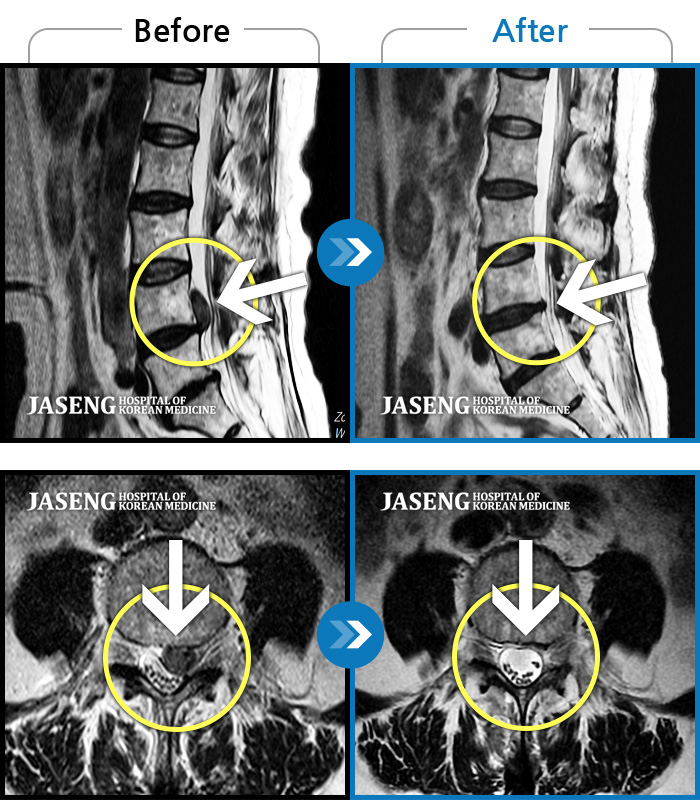

처음 내원 시 허리와 좌측 골반이 많이 아프고, 좌측 다리로 저림과 감각 저하가 있어서 보행이 원활하지 못했으며, 야간통으로 잠도 못 자고 통증 심하여 정상적인 활동이 힘든 상태셨습니다.

2023.09.16 ~ 2024.09.24